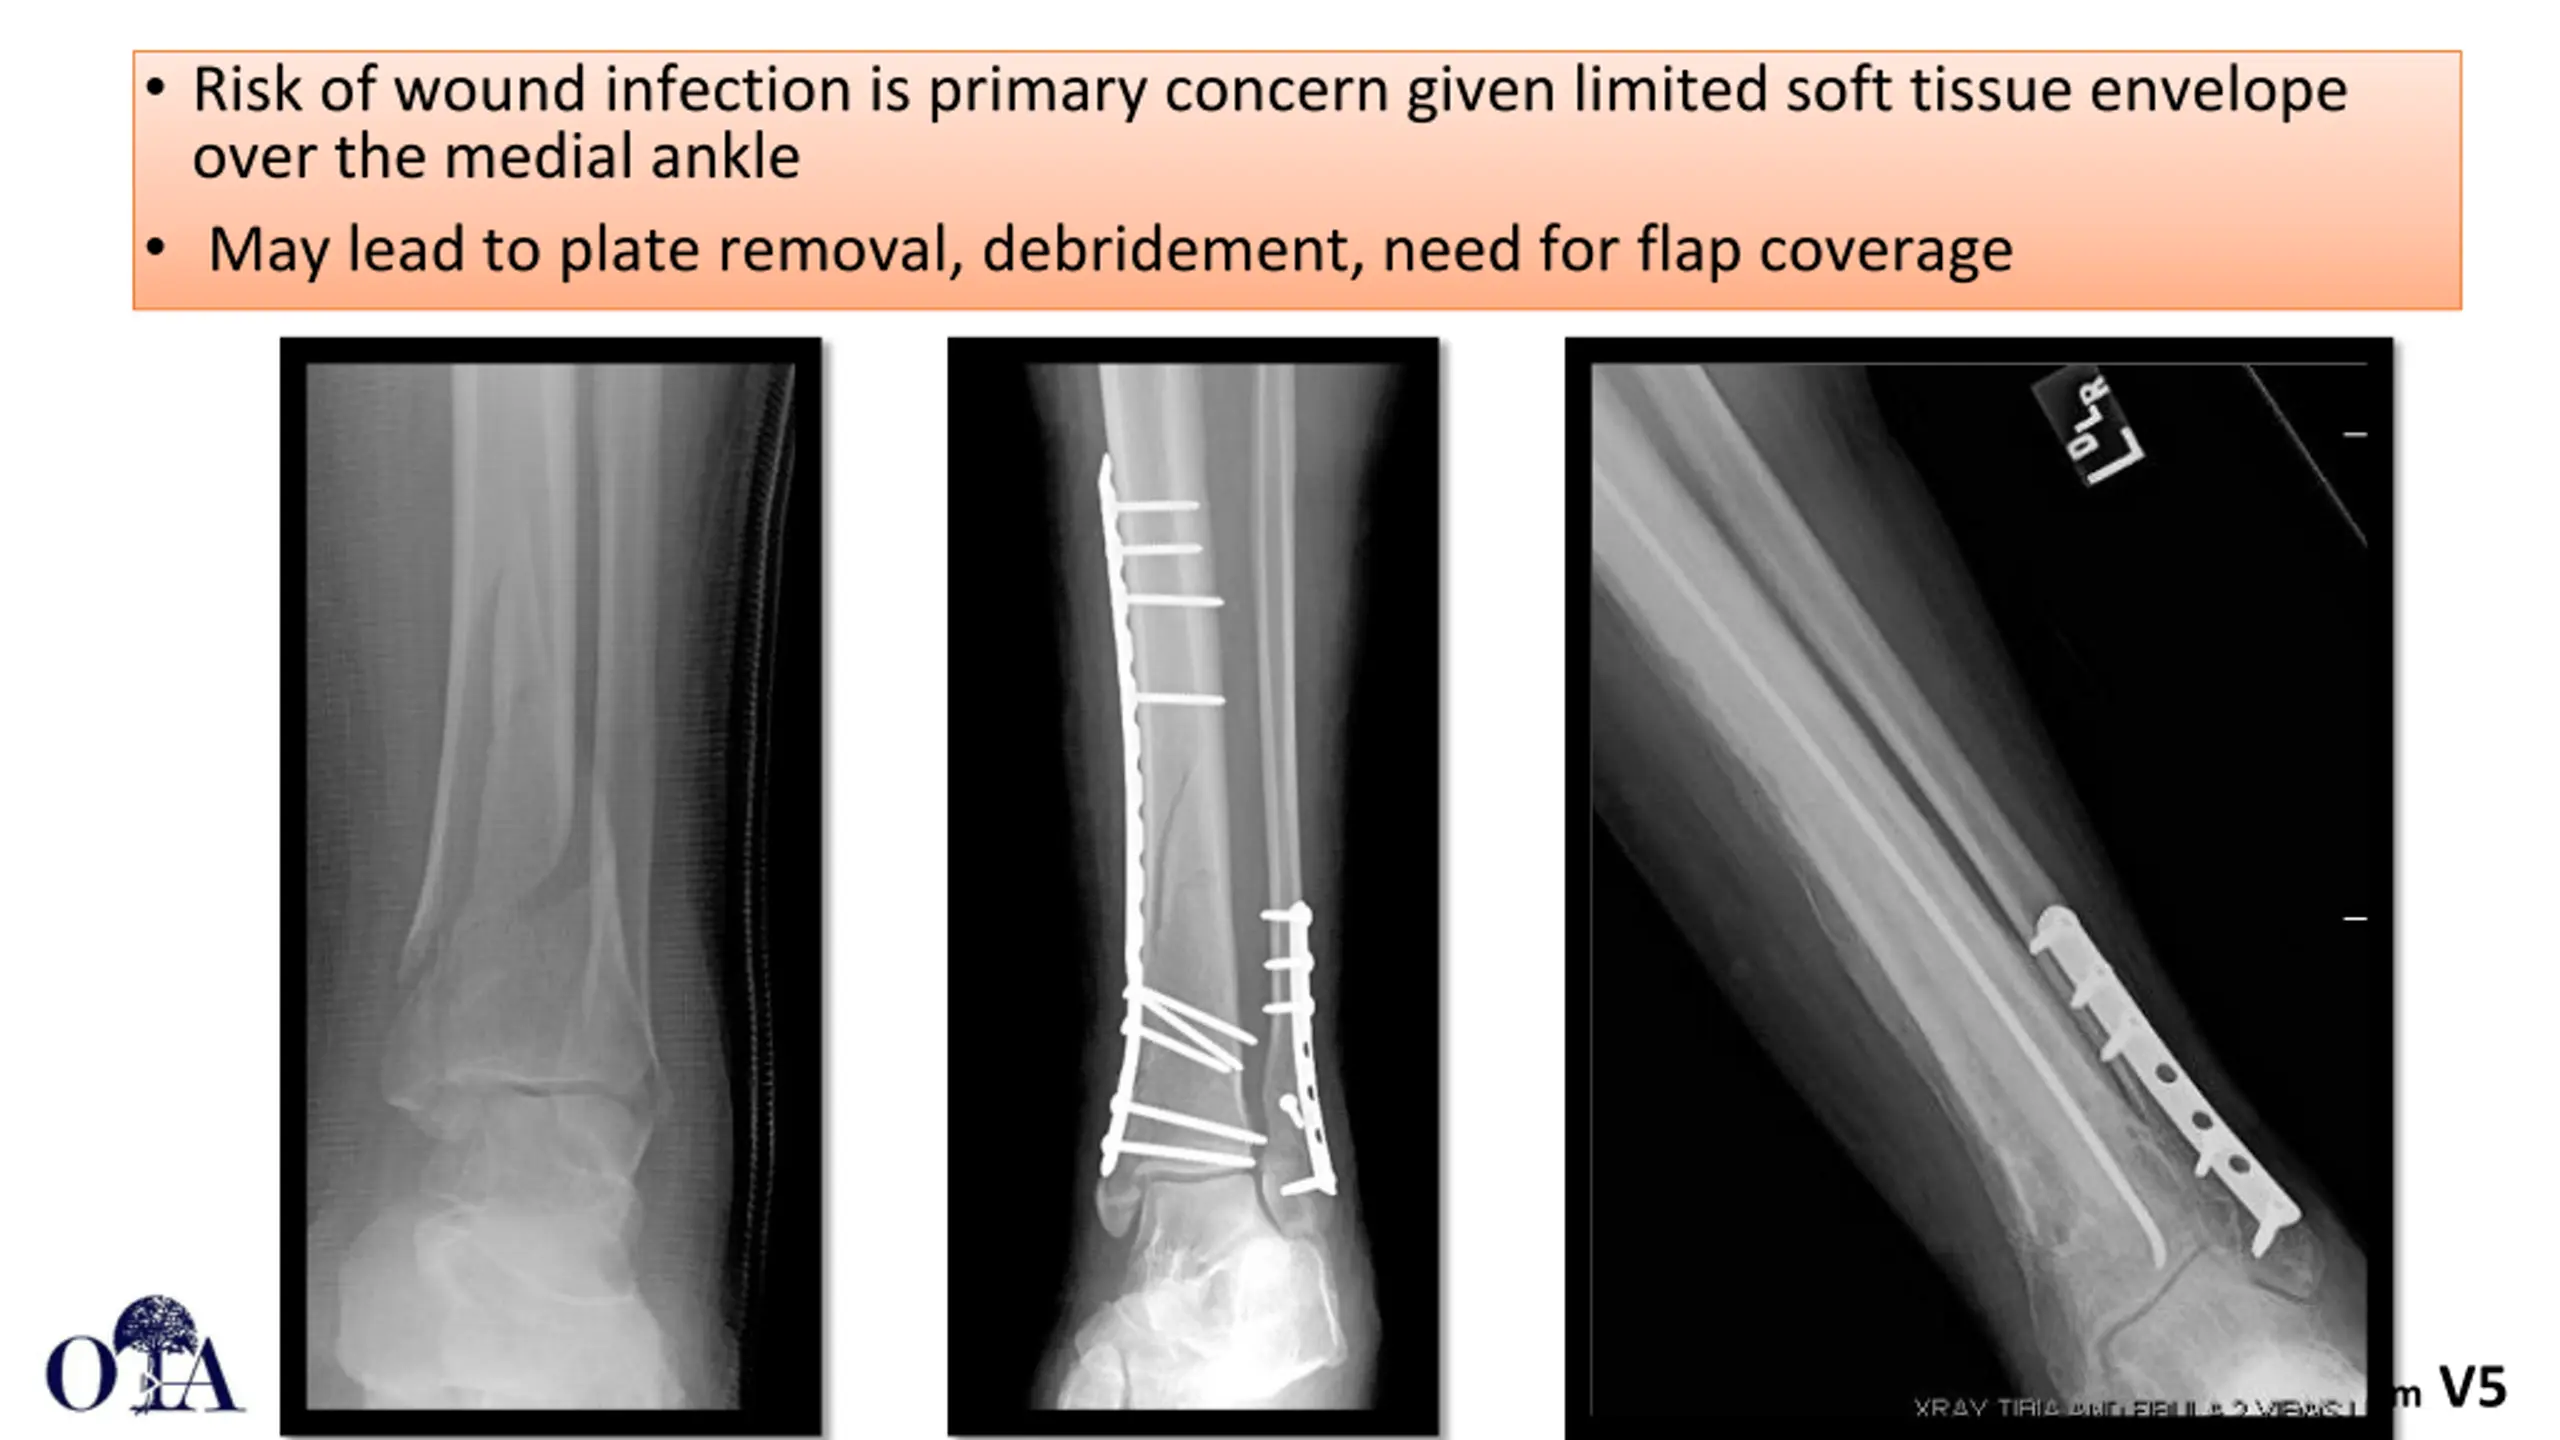

Risk of wound infection is primary concern given limited soft tissue envelope over the medial ankle May lead to plate removal, debridement, need for flap coverage Core Curriculum V5